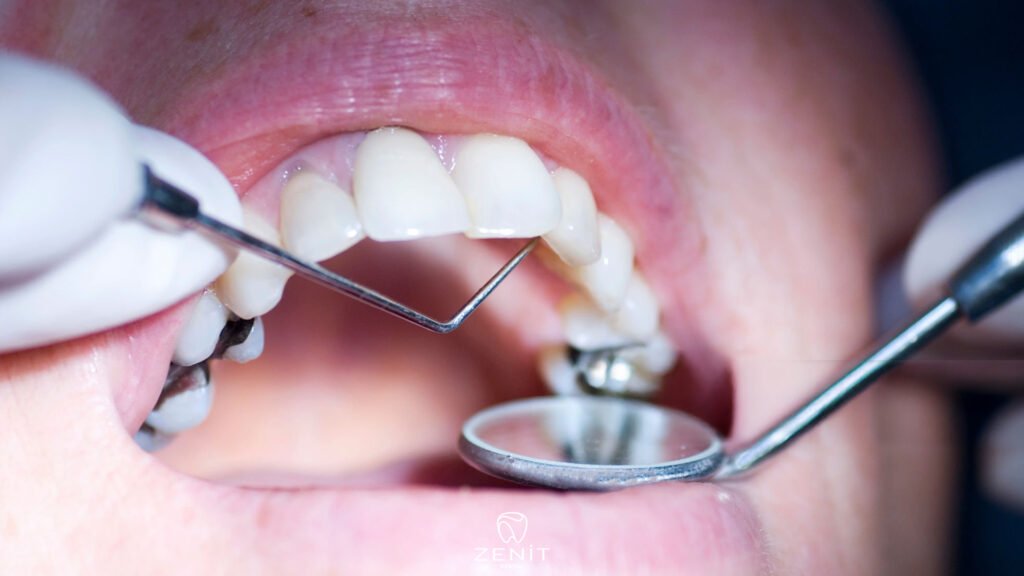

Regular dental check ups should also not be neglected. A simple check every six months allows small problems to be detected before they grow. Of course, dietary habits also matter; instead of consuming sugary foods constantly, it is much better to consume them at specific times in a balanced way.

If you have had a filling for a long time and occasionally feel sensitivity, pain, or an unusual sensation in that tooth, it should not be ignored. This does not always mean there is a serious problem. Sometimes the filling just needs a check up, sometimes a small adjustment is enough, and sometimes everything is perfectly fine and you can simply feel reassured.